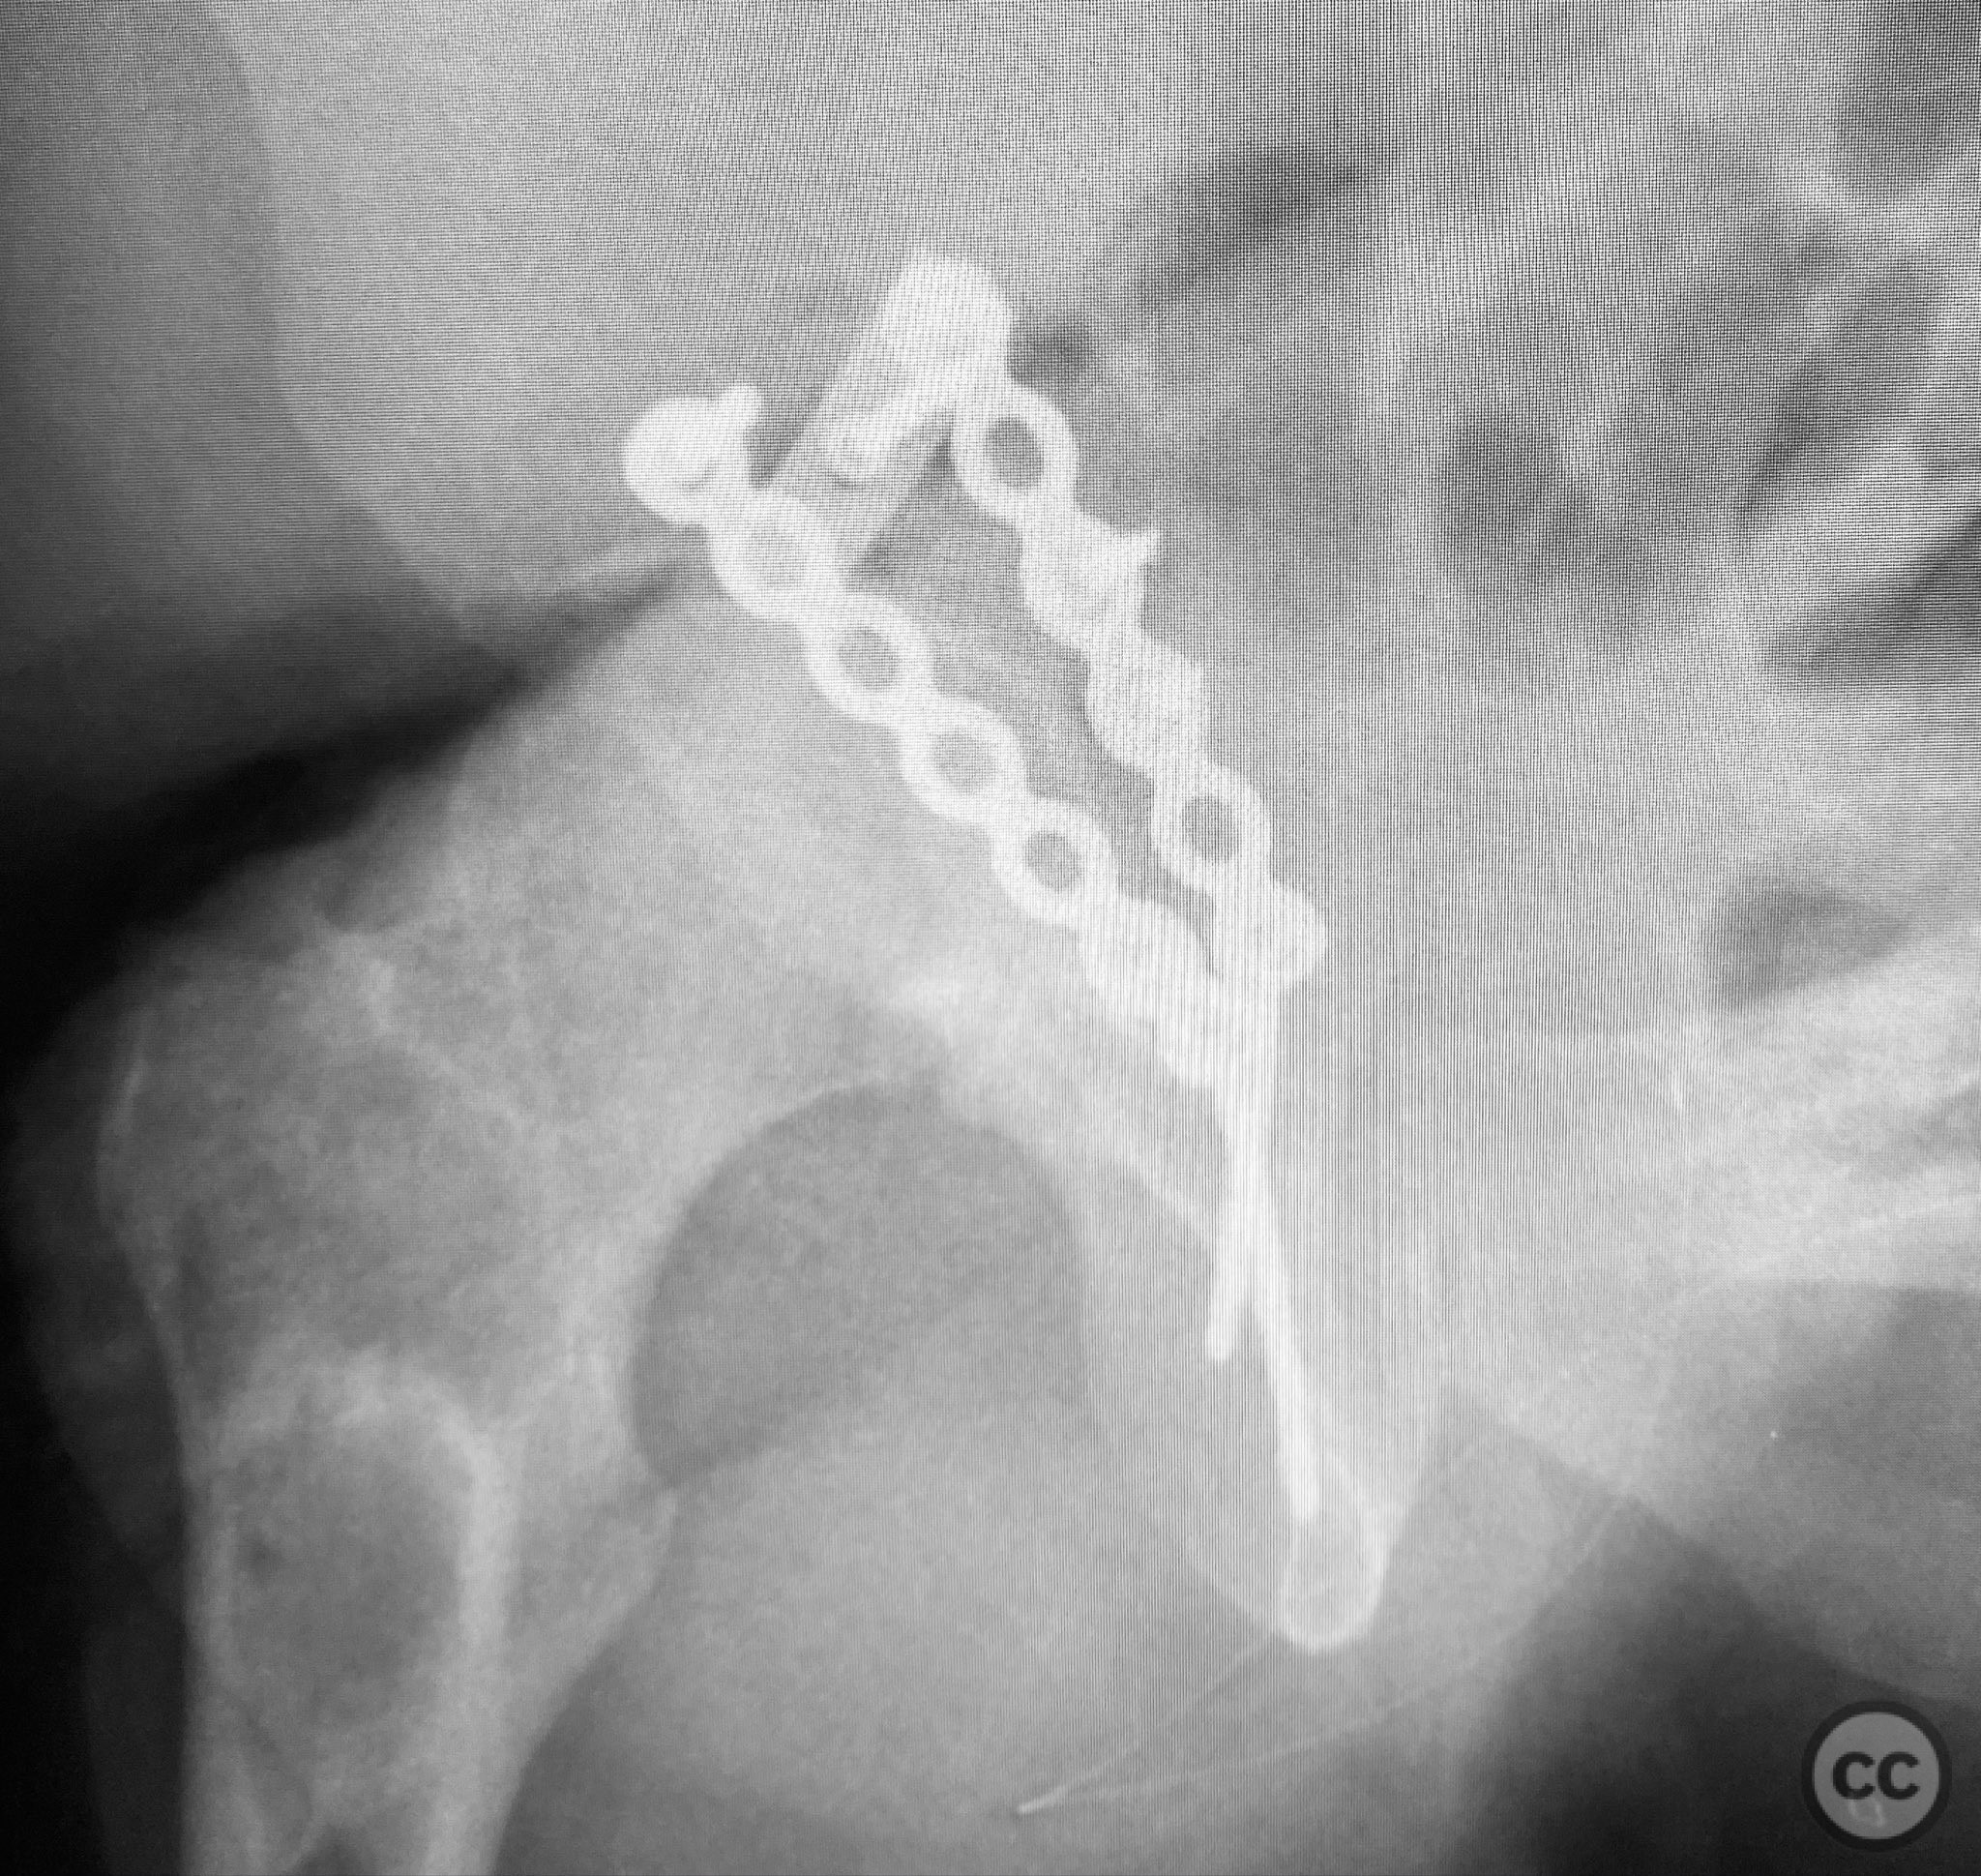

Anatomical surgical approach:  A standard Kocher-Langenbeck approach was performed: a longitudinal incision centered over the greater trochanter, extending proximally along the posterior iliac crest and distally along the femoral shaft. The fascia lata was incised, and the gluteus maximus split in line with its fibers. The short external rotators and piriformis were identified, tagged, and released to expose the posterior column and wall of the acetabulum. The sciatic nerve was identified in the greater sciatic notch region; intraoperatively, it was found to be severely contused, displaced, and uniquely penetrated by a sharp posterior wall fragment. Neuroplasty was performed, freeing the nerve from impalement and surrounding scar tissue. The intra-articular fossa acetabuli fragment was extracted, anatomically reduced, and stabilized along with other posterior wall fragments. A spring hook plate was applied to secure the cranial wall fragment due to its size and comminution.

Operative remarks:

Intraoperatively, the sciatic nerve was found to be not only contused but also impaled by a displaced posterior wall fragment—a rare occurrence in acetabular trauma. Careful neuroplasty was required to release the nerve from direct bony penetration without further iatrogenic injury. Reduction of all articular fragments was achieved under direct visualization, with particular attention to restoring congruity of the acetabular rim and fossa. The use of a spring hook plate provided necessary buttress for the large cranial wall fragment, which could not be adequately stabilized with standard plating alone.

Orthopaedic implants used:   3.5mm reconstruction plate, spring hook plate